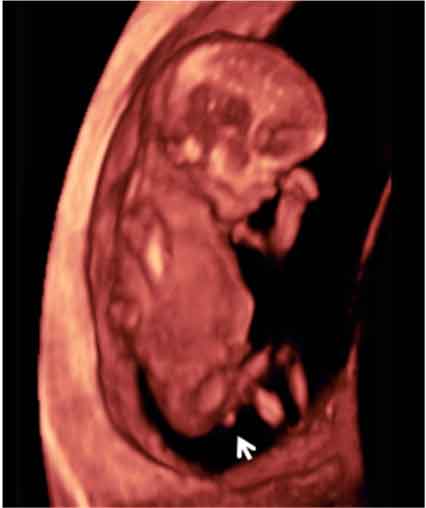

Ecografía 3D de semana 11: Feto de perfil

Perfil en ecografía 3D de un feto de 11 semanas

El tubérculo genital (flecha) apunta hacia abajo, lo que hace muy probable que se trate de una mujer.